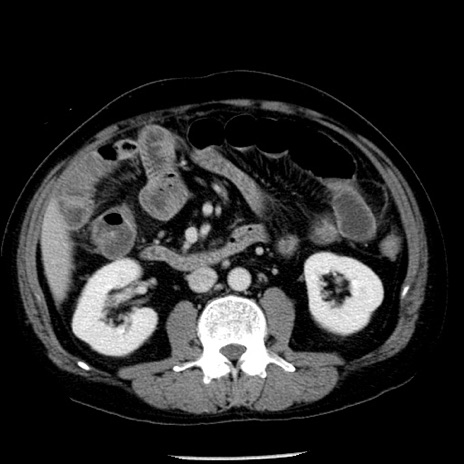

症例29(横断像)

【症例】40歳代男性

【現病歴】2日前から胃痛あり。徐々に周期的な激痛に変化した。本日になっても激痛があるため受診。

【身体所見】意識清明、BT 38-39℃台あり、腹部:膨満、やや硬、右下腹部に圧痛あり。

【データ】WBC 8500、CRP 23.26